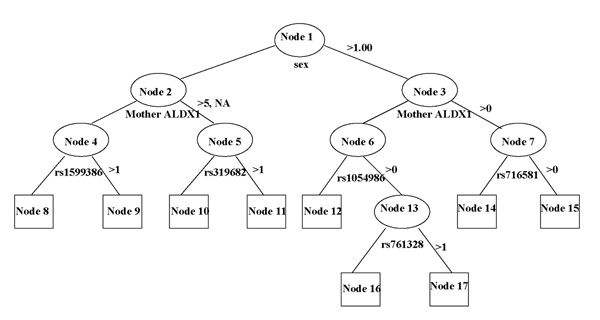

The tree construction consists of two steps: tree growing and pruning. Tree growing is based on recursive partitioning. The classification tree for ALDX1 as the single outcome is shown in Figure 1, while Figure 2 depicts the classification tree for comorbid ALDX1 and smoking.

Figure 2.

The pruned tree at the significance level of 0.0001 for comorbid ALDX1 and smoking using Illumina SNP data. We use circles and boxes to represent internal and terminal nodes, respectively. Under each internal node is the covariate that is used to split the node.

In Figure 1, the root node at the top contains all study samples. We use circles and boxes to represent internal nodes and terminal nodes, respectively. A splitting rule consists of a covariate and its corresponding threshold. As shown in Figure 1, sex is selected to split the root node with males to the right daughter node and females to the left daughter node, underscoring prominent sex difference. The selection of such a split is based on a specific goodness of split measure such as entropy [6]. The objective of the split is to produce two daughter nodes (numbers 2 and 3 in Figure 1) such that the within-node distribution of the phenotype such as ALDX1 in Figure 1, is as homogeneous as possible. Specifically, suppose that we consider splitting node t, which can be the root node, and that the outcome variable has q levels, which is 4 for ALDX1 and 8 for the combination of ALDX1 and smoking. The entropy-based goodness of split is defined as

and  . The split based on the sex variable for the root node in Figure 1 was selected because it yielded the highest i(s) after evaluating all possible splits of the root node using all covariates and all SNPs.

. The split based on the sex variable for the root node in Figure 1 was selected because it yielded the highest i(s) after evaluating all possible splits of the root node using all covariates and all SNPs.

We adopted the bottom-up method described in Zhang and Singer [6] to delete those superficial or unreliable splits. A χ2 testing statistic for a 2 × q contingency table was calculated for each internal node. For example, in Figure 1, we have the 2 × 4 table as shown in Table 1 for the root node and the χ2 value equals 189.8 for testing the independence of cell counts in the table. After the χ2 values are obtained for all internal nodes, we can follow the suggestion of [6] by prespecifying a significance level (e.g., 0.01) and void all splits whose χ2 values as well as the χ2 values in the subsequent splits do not exceed the predetermined threshold. This pruning step resulted in the tree in Figure 1 for ALDX1.

Using the method described above, we obtained an initial tree with 139 nodes for ALDX1. At the significance level of 0.0001 based on a 2 × 4 contingency table, a tree with 39 nodes is determined. At significance level of 0.00001, a tree with 19 nodes is selected as shown in Figure 1. Figure 1 identified six important SNP markers that appear to be significantly associated with alcoholism. We list the SNP markers that are selected when ALDX1 or ALDX1 and smoking are used as the responses in Table 2.